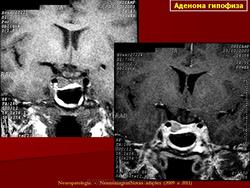

ГМ. Аденома гипофиза 1. +

Аденома гипофиза.